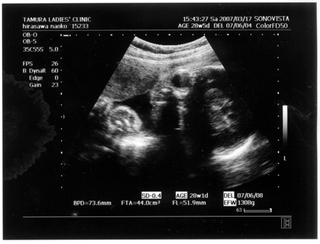

× [PR]上記の広告は3ヶ月以上新規記事投稿のないブログに表示されています。新しい記事を書く事で広告が消えます。 9ヶ月(32週と5日) 体重:2072g BPD(頭を上から見た耳から耳の幅のような感じ):84.6㎜ FTA(お腹の断面):60.8平方㎝ FL(大腿骨長 太ももの骨の長さ):61.2㎜ 9ヶ月(35週と2日) 体重:2583g BPD(頭を上から見た耳から耳の幅のような感じ):90.2㎜ FTA(お腹の断面):72.8平方㎝ FL(大腿骨長 太ももの骨の長さ):64.8㎜ 久しぶりの記事アップです ![]() なんだかあっという間にGW終わってしましましたね~ ![]() きのうは雨のせいでだらけてしまって、記事書く予定ができませんでした ![]() ダンナっちには『雨降って ナオコ 動かず』といわれています・・・ ![]() さてさて、5月2日(35週と2日)の内診では、 子宮口が1センチ開いてきてることが発覚 先生に「もう少し入れておいてよ 張ったら休まなきゃダメ」と言われ、 薬 まで出されました。子宮の筋緊張状態をやわらげて、早産を防止 するんだそうです。 「慣れるまでは心臓がドキドキしたり、 手が震えたりしますけど、大丈夫ですから」 と先生から説明を受けて、家で飲んでみると、 ほんとにドキドキ して、手もピクピク してきて、なんかラリった妊婦状態で不思議でした。 今週に入って、だいぶ慣れたようでそんなにラリっては いないけど、飲んでから1時間くらいは運転を控えています ![]() ベイビー自体は2500gをすでに超えて、動きも活発で元気にしています ![]() 1センチ開いてもなかなか進まないこともあるし、どうなるかはわかりません ![]() でも、ベイビーがお腹から出てきて自分で呼吸をするために、 必要な肺のサーファクタント(界面活性物質)の分泌は、妊娠33~36週ころから になります。 哺乳反射といって、ベイビーがおっぱいを飲むための反射的に吸い付く能力は 32~34週で完成するそうです。 網膜の血管が完成するのは35週前後だそうです。 つまり、わたしは今週臨月(36週)に入りましたが、 やっぱり正期産である37週からの出産が望ましいみたいです ![]() ![]() 医療も発達してきてるし、 ほぼ完成しているので生きられないことはぜんぜん無いんですけど、 十分に成長して「時」が満ちて生まれるのが一番みたいですね~ ![]() 「はやく会いたいけど、あと3週間くらいお腹の中にいてね~」 とベイビーに言っています ![]() 薬をもらってから、「張り」を意識するようになったんですけど、 けっこう張るんですよね~ 張るとなんとも動きづらい ![]() パンパンで重みのある厚手のゴムボール を持って歩くような・・・そして、 膀胱圧迫![]() ![]() ![]() トイレ行くにも駆け込む動作がつらい 歩けない![]() 、走れない![]() ![]() 悲惨な結末 ![]() ![]() ![]() ![]() を迎えまいとして、キュッと閉める運動をせざるをえなくなります・・・ ![]() PR